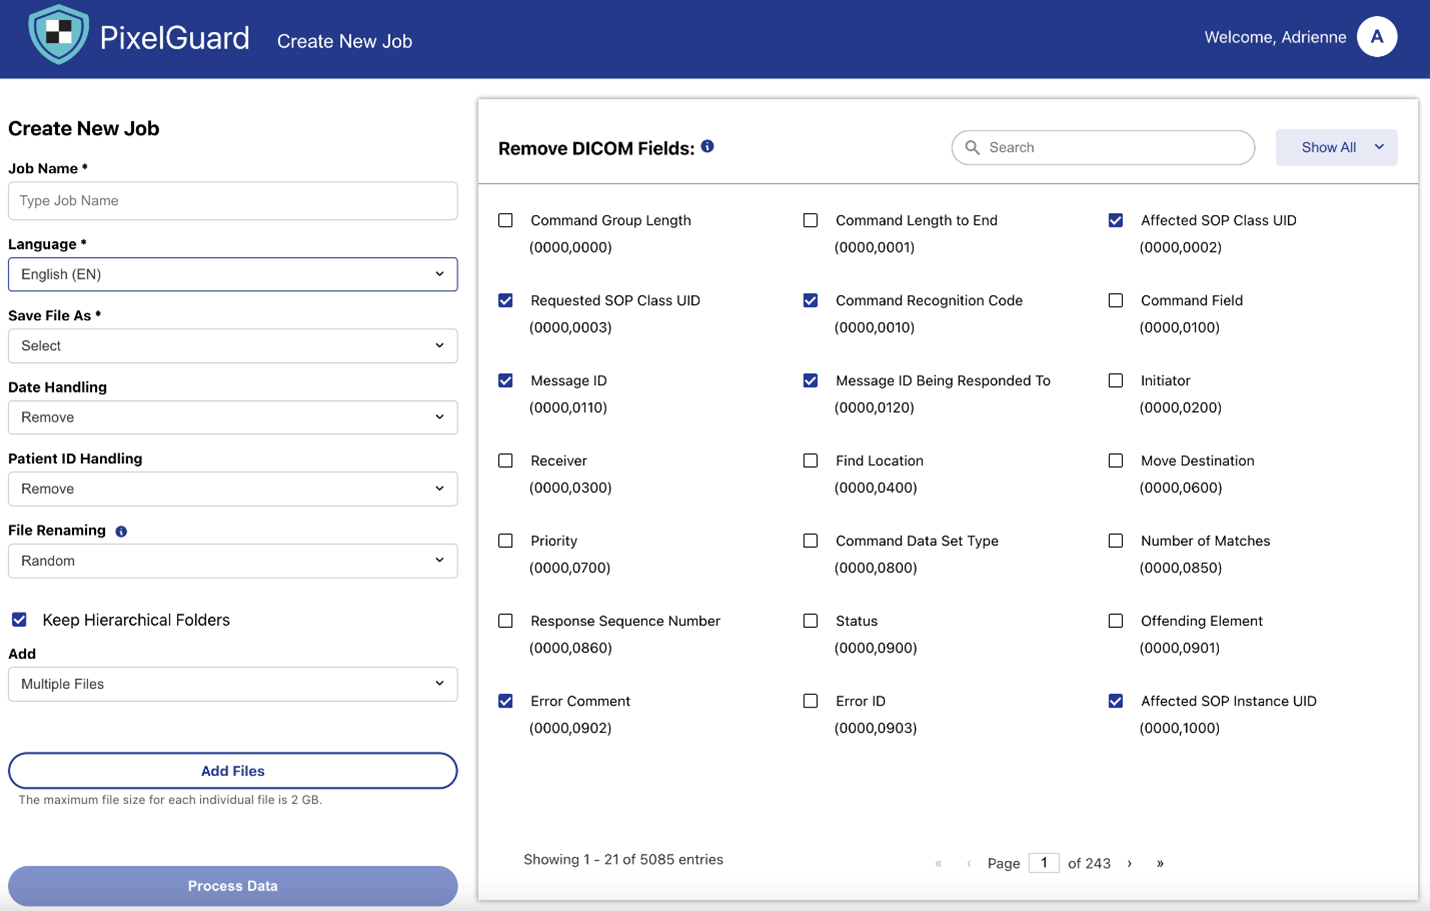

PixelGuard—built on Amazon Web Services (AWS) and created by Northwestern University Assistant Professor and Founder of Xtasis, LLC, Dr. Adrienne Kline—is an advanced software solution that deidentifies medical images while preserving clinical relevance and efficacy. It uses over 75 state-of-the-art AI-driven models capable of detecting and redacting multilingual, multi-orientation text across all major formats (DICOM, JPEG, PNG, NIfTI, etc.), alongside configurable metadata anonymization. With an intuitive UI, enterprise SSO, and in-tenant deployment (no data egress), PixelGuard delivers secure, compliant, and high-throughput image de-identification. PixelGuard is available on AWS Marketplace. ScaleCapacity—an AWS Partner—was instrumental in the development of the UI, cloud infrastructure, and deployment to AWS Marketplace.

The ingestion layer provides a user interface and an API to submit a medical image for de-identification. The API can also be used by a third-party medical device manufacturer to provide the redaction ability. Prior to the ingestion, the web UI and API can be secured with enterprise identity provider based authorization. Along with ingesting the image needing de-identification, this layer must also capture the specific de-identification configuration, which defines which fields need to be redacted from the image. For common redaction scenarios such as redaction to comply with HIPAA regulations, predefined field sets are defined and recorded.

The following images provide an overview of the image redaction experience using PixelGuard.